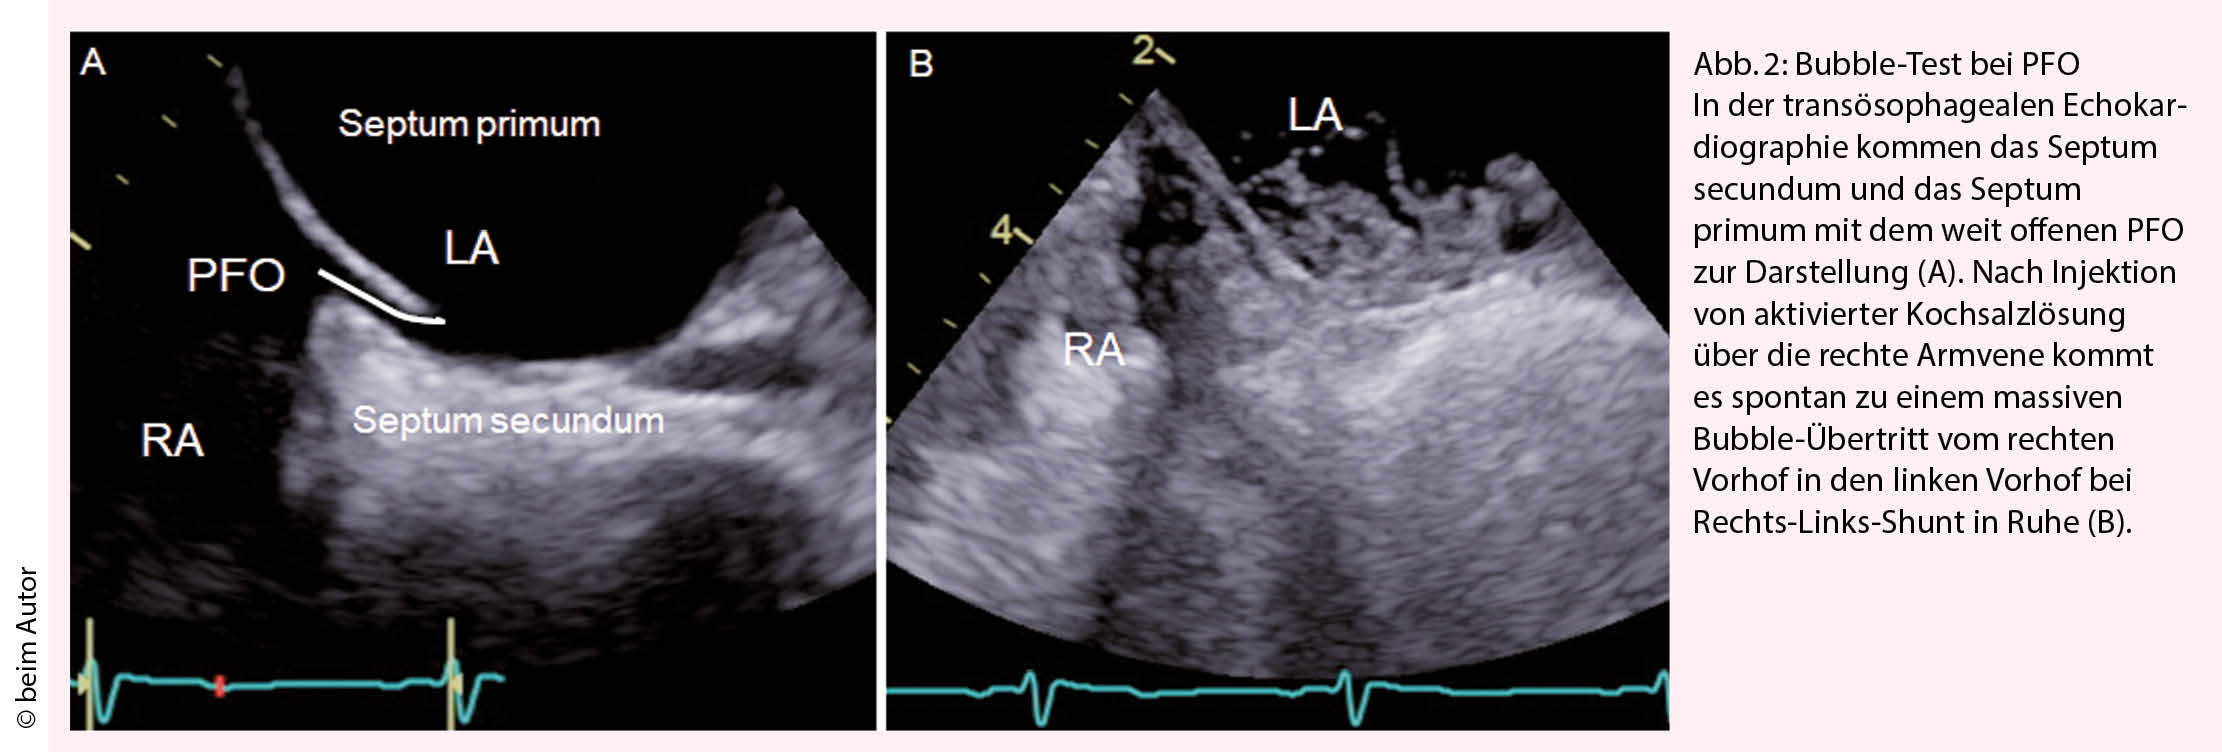

Das Elektrokardiogramm oder ein Langzeit-EKG von 24 bis 72 Stunden, ev. auch eine Langzeitaufzeichnung, sind nötig, um ein Vorhofflimmern auszuschliessen. Die Wahrscheinlichkeit, dass ein okkultes Vorhofflimmern vorliegt, ist altersabhängig. Bei jungen Patienten mit normaler Herzfunktion ist das Vorhofflimmern eine Rarität. Bei Patienten über 60 Jahren oder bei vergrösserten Vorhöfen wird die Wahrscheinlichkeit, dass ein Vorhofflimmern vorliegt, höher und die entsprechende Suche nach Vorhofflimmern wichtiger. Die transthorakale Echokardiographie dient zum Ausschluss einer kardio-embolischen Quelle. Liegt keine Pathologie am Myokard oder den Klappen vor oder besteht der Verdacht auf eine paradoxe Embolie durch das PFO wird eine transoesophageale Echokardio­grafie (TEE) angeschlossen. Meist wird bereits bei der transthorakalen Echokardiografie, sicher aber bei der TEE ein Bubble-Test durchgeführt (Abb. 2) um festzustellen, ob ein Rechts-Links-Shunt in Ruhe vorliegt oder mittels eines Valsalva Manövers provoziert werden kann. Die TEE ermöglicht zum einen den Ort des Rechts-Links-Shunts zu eruieren, zum anderen Shuntvitien wie ein Vorhofseptumdefekt, falsch mündende Lungenvenen oder eine pulmonale A-V Malformation auszuschliessen. Mittels TEE wird die Morphologie und Anatomie des PFO und des Vorhofs visualisiert, was wichtig ist für einen eventuellen PFO Verschluss. Die Evaluation der Grösse des PFOs in der TEE ist jedoch problematisch, da das Septum primum deckelförmig mehr oder weniger aufgeht und der Bubble-Übertritt damit von der Qualität des Valsalva-Manövers abhängt (Abb. 2). In der TEE kommt in der 2-D Darstellung die schlitzförmige Öffnung des PFO meist als kleine Lücke von 1-4 mm zur Darstellung. In Wirklichkeit variiert die anatomische Grösse des PFO von 4 bis 16 mm, im Mittel beträgt sie 8 ± 3 mm (6, 7).